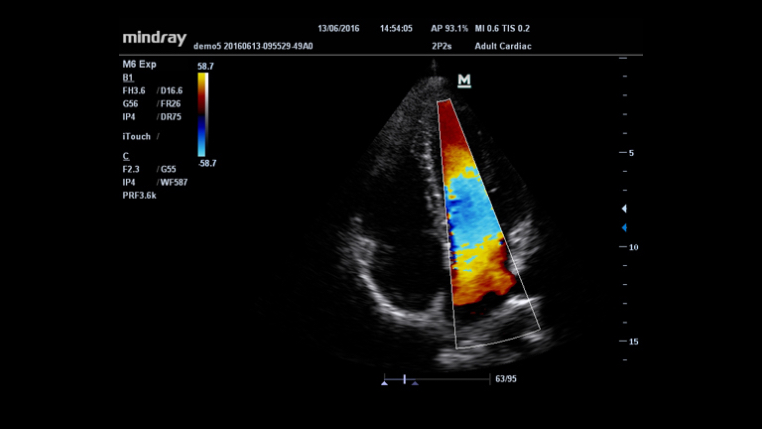

HR Flow?

Funci√≥n √Їnica de Mindray: Una funci√≥n √Їnica de Mindray: realice un seguimiento continuo del flujo de color y optimice la mejor posici√≥n del cuadro de color y el mejor √°ngulo en la adquisici√≥n de im√°genes en tiempo real.